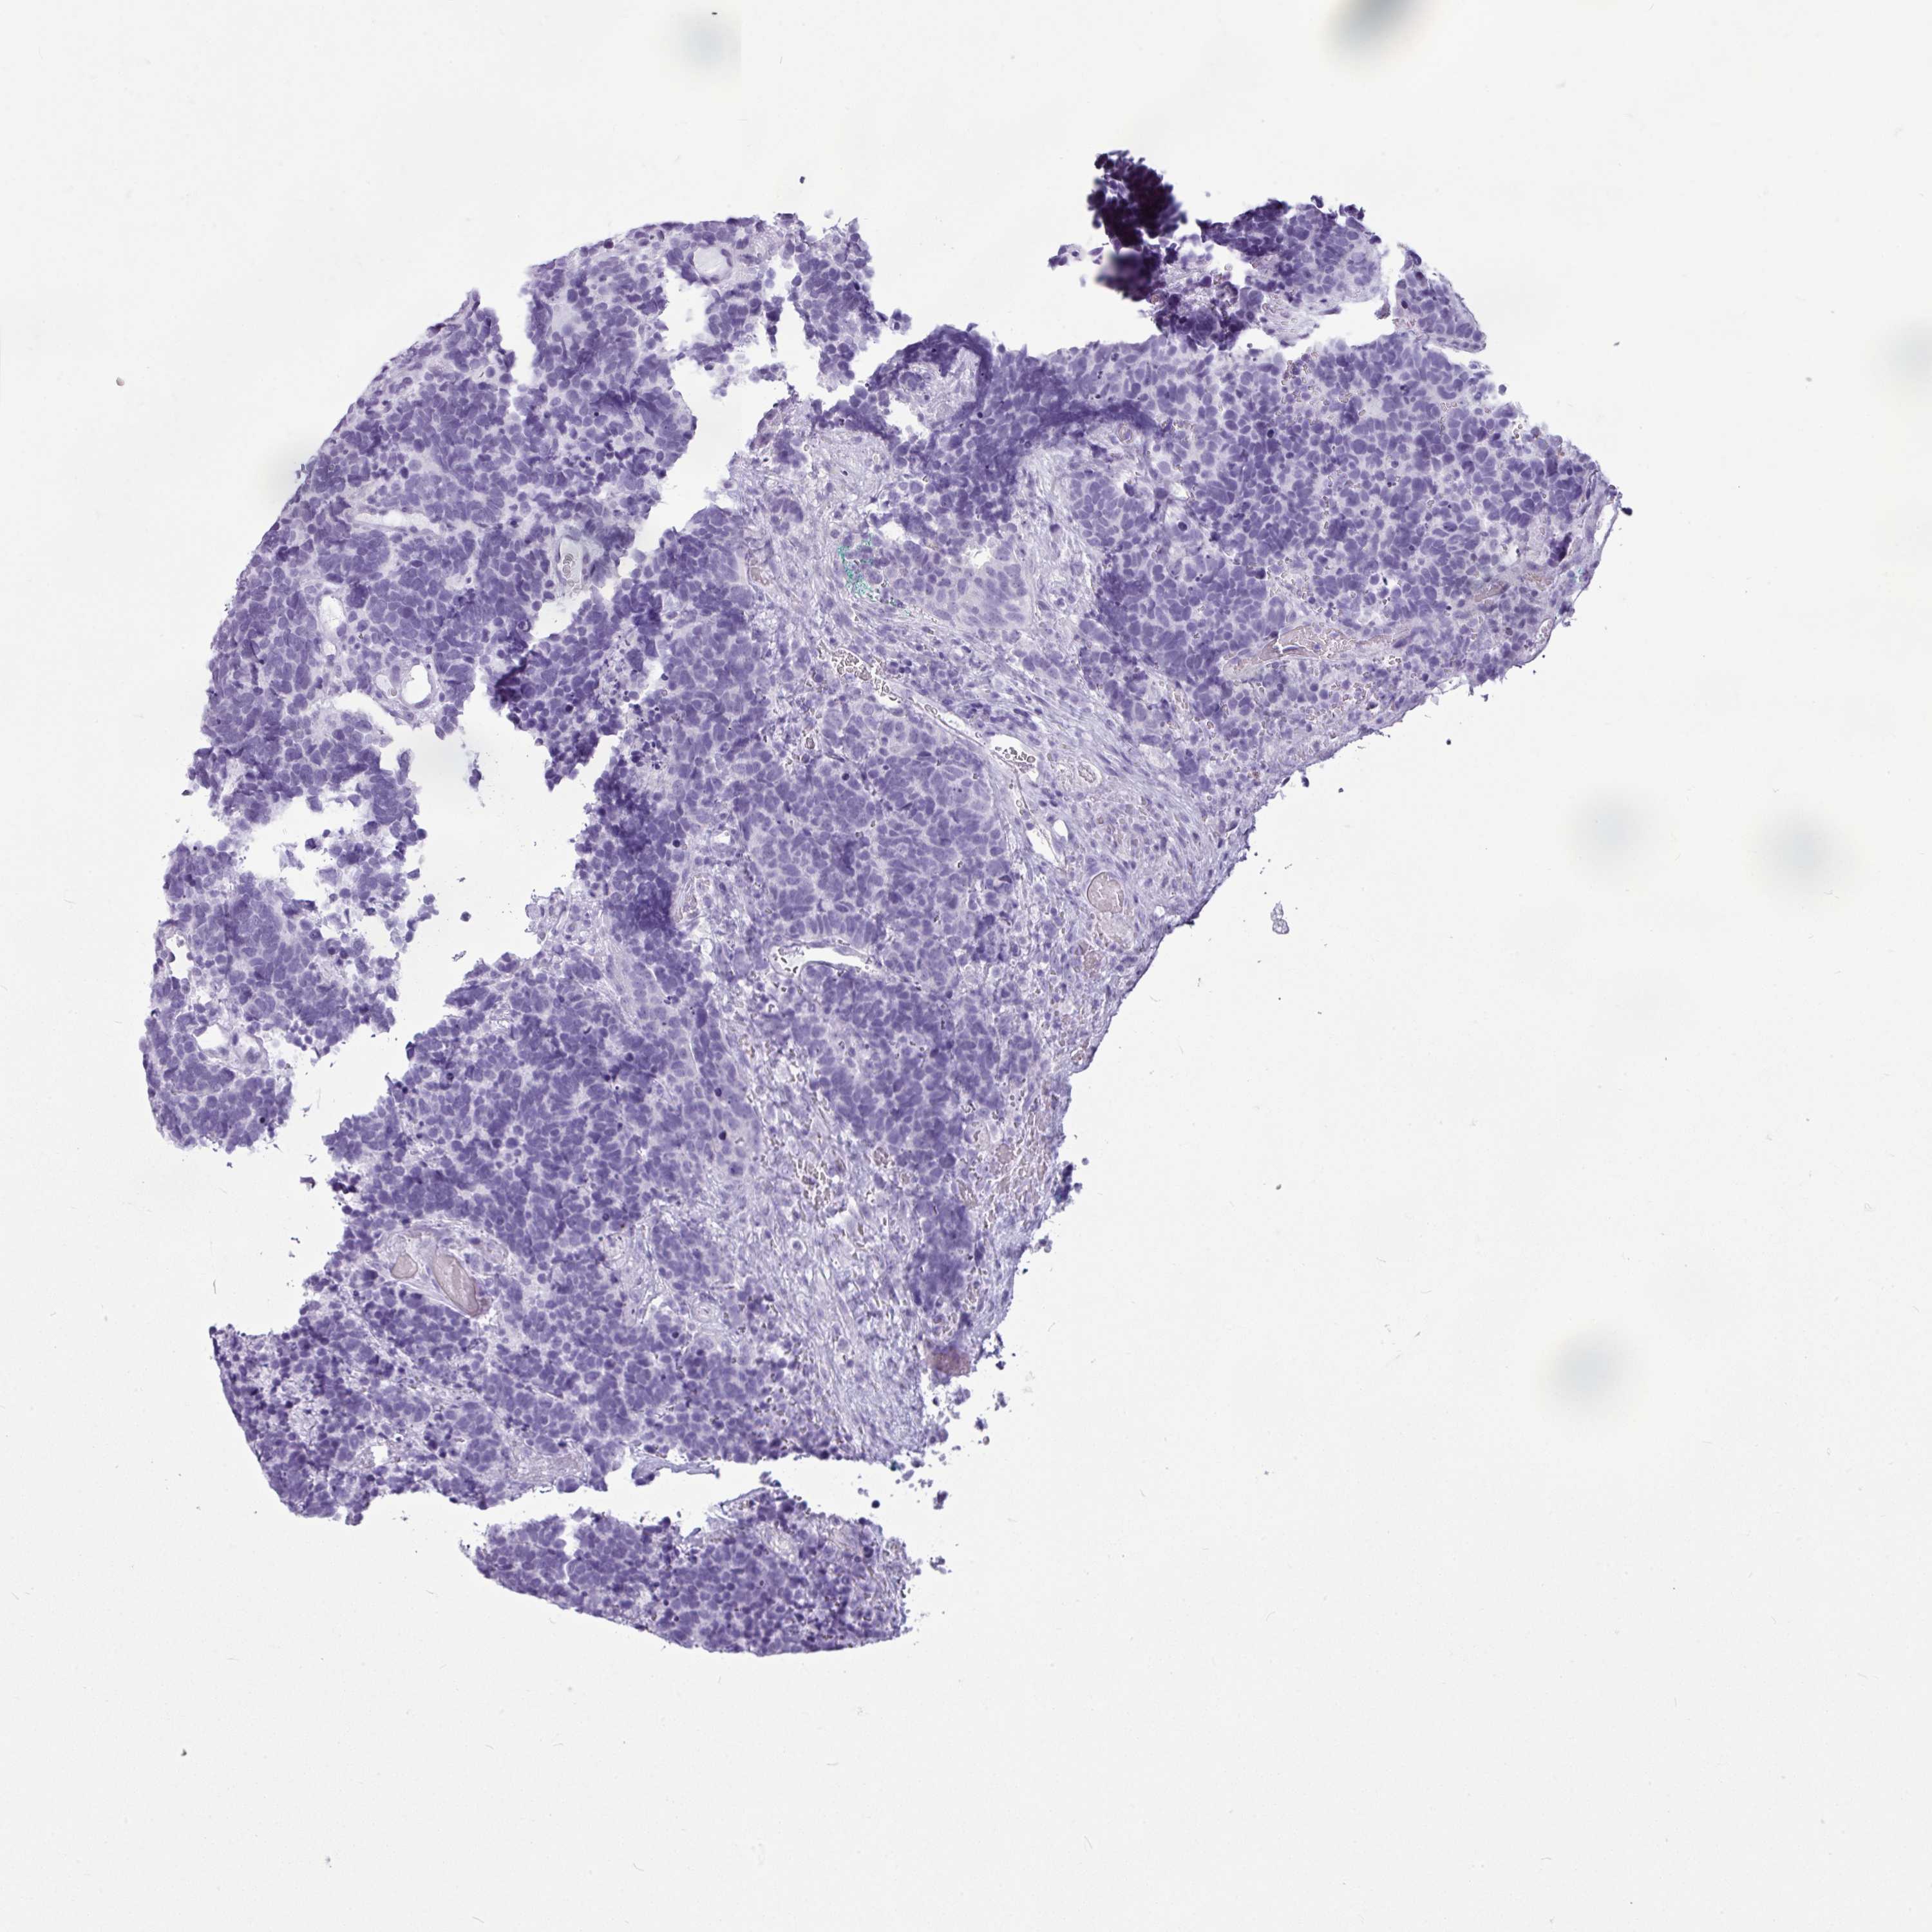

AMY1C